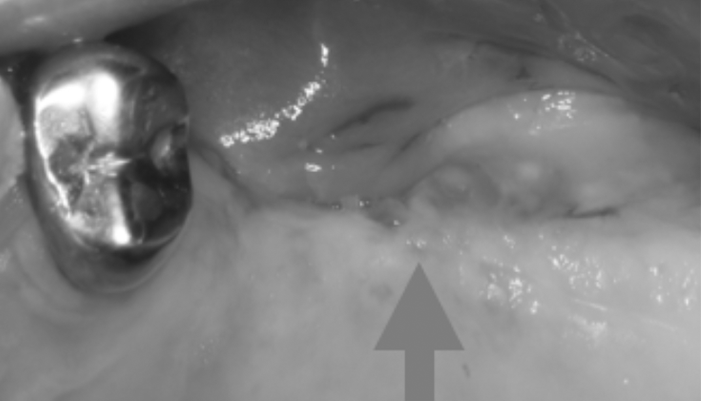

治療前

患者様は「インプラントした部分を長く安心して使える状態にしたい」とのご希望で来院されました。初診時は、すでにインプラントが埋入されており二次手術前の状態でしたが、角化歯肉の幅が不足しており、将来的な清掃性や安定性に不安がある状態でした。そこで、単純な二次手術のみではなく、インプラント周囲に十分な角化歯肉を確保する処置を併用し、清掃しやすく長期的に安定しやすい環境を整えました。

| 主訴 | インプラント治療の続き。 |

|---|---|

| 治療期間 | 1回 |

| 治療費 | ¥33,000(税込) |

| 治療内容 | インプラントの2次手術として歯肉形成を行いました。硬いしっかりした歯茎(角化歯肉)がないと将来的にインプラントが炎症を起こしやすいためです。 |

| 治療のリスク | 腫れ・出血などが生じる場合があります。 |